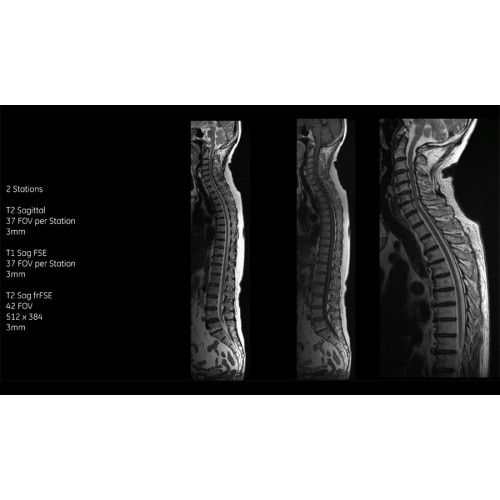

Система SIGNA Pioneer воплощает поразительные достижения в области визуализации. Передовая технология Total Digital Imaging (TDI) позволяет добиться большей четкости изображений и на четверть повысить соотношение сигнал/шум.

• Технология Digital Surround Technology (DST) — это новая технология объемной оцифровки данных, объединяющая сигналы от каждого элемента катушки. Прекрасное соотношение сигнал/шум и чувствительность поверхностных катушек в сочетании с превосходной однородностью и высокой проникающей способностью встроенной радиочастотной катушки — все это позволяет создавать качественные изображения не только позвоночника, но и всего тела.